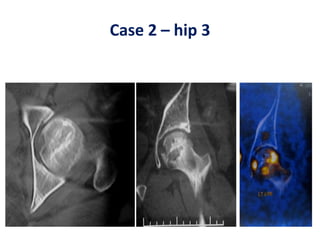

Case 2 – hip 3